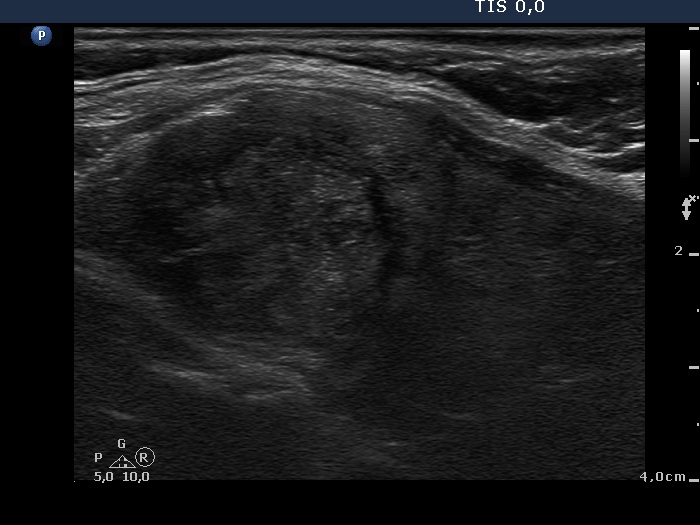

TIRADS - case 1147

Follow-up examination two years after the first visit (ultrasonographic picture 5)

Upper part of the left lobe, longitudinal scan.